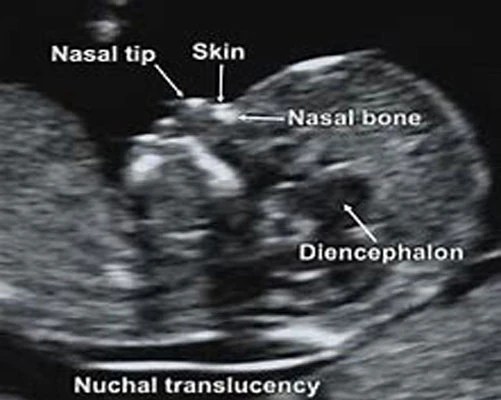

At 12 Weeks: Nuchal Translucency ScanThe nuchal translucency (NT) scan, or “12-week scan,” is an ultrasound performed in the first trimester between 11.5 weeks and 13 weeks, six days. This scan is combined with a blood test that looks at two specific hormones of pregnancy: the free-Beta hCG and PAPP-A (pregnancy associated plasma protein A). This combined test is an extremely accurate non-invasive screening test available to help identify a fetus at risk for Down syndrome as well as other chromosomal abnormalities and some major structural abnormalities. The sensitivity of this only recently eclipsed by NIPT. An ultrasound screening test is non-invasive and does not have any side effects or complications.

At the end of the first trimester, there is usually a small amount of fluid beneath the skin of the fetus at the back of the head and neck.

This fluid is called the nuchal translucency (NT), and can be easily and accurately measured to within a tenth of a millimetre.

When there is extra fluid and the NT measurement is thicker than normal, there is an association with chromosomal anomalies such as Down syndrome and some structural abnormalities in the fetus. Not all babies with an increased NT measurement have Down syndrome or any structural abnormality.

The extra fluid at the back of the head and neck usually disappears by 18 weeks. The fluid in itself is not an abnormality and does not harm the baby but may simply be the sign of a potential problem. The baby is measured from head to bottom to determine the crown-rump length and the nuchal translucency is measured. These measurements are entered into the computer program with the patient’s date of birth and the first trimester biochemistry blood test. The computer then calculates the patient’s age-related risk for Down syndrome and the new individual risk for this pregnancy.

The findings are then discussed with the patient. The combined NT result will provide the patient with a risk assessment. This will either be a high risk (risk is greater than 1 in 300) or a low risk (risk less than 1 in 300). As this is a screening test and not a diagnostic test, even with a low calculated risk, Down syndrome is not completely excluded and can still occur occasionally.

Accuracy of Nuchal TranslucencyWhen the ultrasound is combined with the first trimester blood test (BhCG and PAPPA) and nasal bone, the detection rate increases to 95%.

This causes a wide range of both physical disability and learning difficulties. At the moment there still isn’t a completely safe test that will tell you that your baby definitely does or doesn’t have Down’s syndrome, but the NHS offers everyone combined first trimester screening, which is a test performed at around 12 weeks using a combination of ultrasound scan findings and a basic blood test to assess the likelihood of whether your baby is or isn’t affected. The key ultrasound marker at this stage is the nuchal translucency measurement, or the space at the back of the baby’s neck. At this stage in the baby’s development it is normal for some fluid to build up in this space at the back of the baby’s neck – it happens to every baby so a little bit of fluid is entirely normal, but a baby with problems will often retain more fluid and the nuchal translucency measurement is increased.